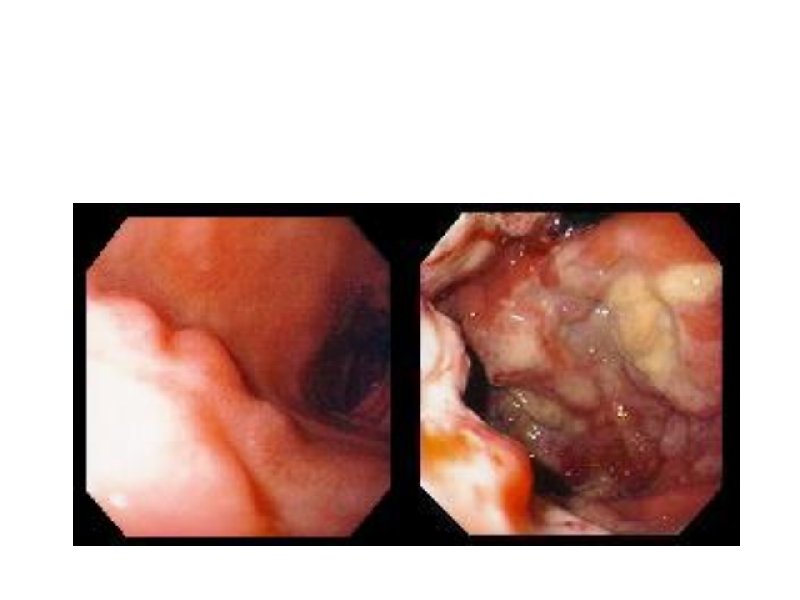

Наружные лимфоузлы при неходжкинских лимфомах